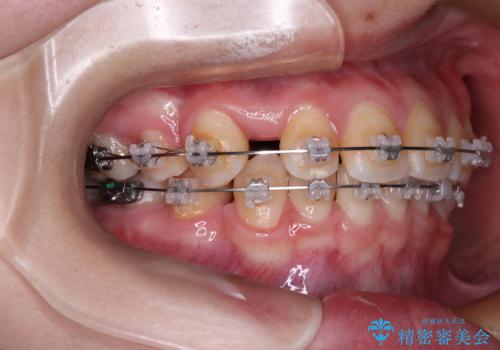

- 矯正装置

- クリアブラケット

- 転勤により東京へ移られることになり転院先を探されていた患者様です。ワイヤー矯正の途中での急な転勤なうえ、今後2~3年以内に再度転勤になる可能性もあるというご事情でした。

そのため、限られた期間内に効率よく治療を完了するために、「抜歯スペースの確実な閉鎖」「深い噛み合わせ(過蓋咬合)の改善」の2点を主軸とした治療計画を立てました。

結果的に1年半で、再度転勤になる前に治療を終えることができました。